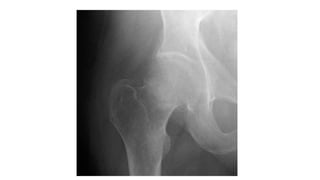

This document discusses femoral fractures, categorized by their location and severity, with classifications such as Garden classification. It outlines the types of fractures, including valgus impacted, non-displaced, partially displaced, and fully displaced, along with their surgical treatment options. Additionally, it briefly describes distal femur fractures, which occur just above the knee joint.